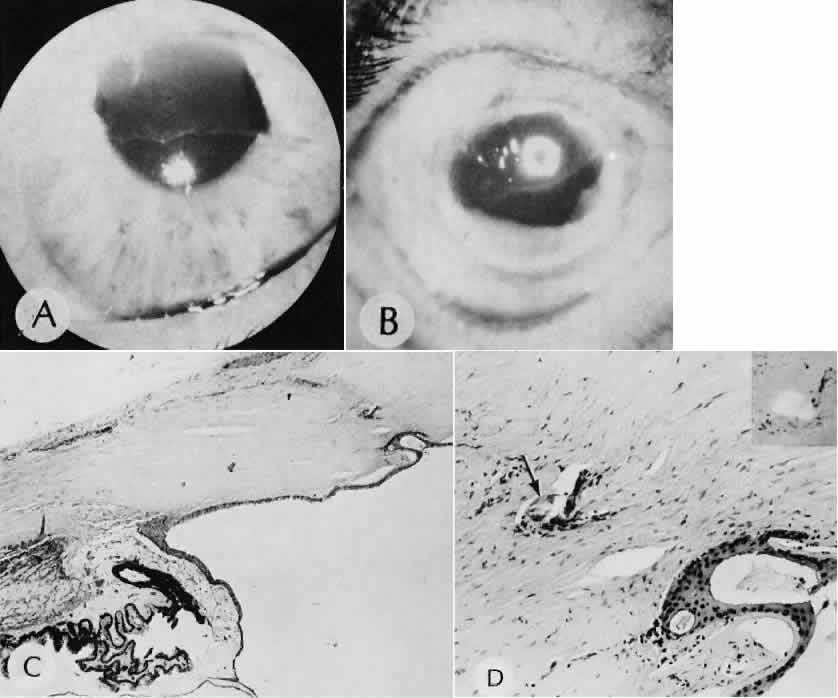

| All ocular surgical procedures are associated with potential complications. A

complication is a deviation from the natural course of the expected

tissue response after a surgical procedure and, in the case of ocular

surgery, usually results in a compromise of ocular function. Complications

may arise from the surgical procedure itself or be the result

of an aberration of the wound healing process. All surgeons will encounter

surgical complications. Eyes afflicted with severe or multiple

disease processes are more likely to develop complications. Early recognition

and a thorough understanding of these deviations from normal allow

for more effective therapeutic intervention.86 Many complications originate from so-called surgical confusion (Fig. 24). Most arise from a lack of knowledge, a lack of judgment, or problems in perception. At times, lack of attention to detail in preoperative planning may lead to a drug reaction, inadequate anesthesia, misplacement of incisions and sutures, or a patient who is unable to control a cough reflex. What is recognized histologically as the immediate cause of the problem may well have its origin in improper planning of the procedure. CATARACT EXTRACTION Intraoperative Complications Complications occurring from the time the patient enters the operating room until the patient leaves the operating room are considered intraoperative.87,88 Misplacement of an anterior segment incision too far anteriorly into the cornea may create an unacceptable degree of scarring or astigmatism, whereas misplacement too far posteriorly (Fig. 25) may cause the incision to enter the ciliary body instead of the anterior chamber, an especially serious event in glaucoma filtering procedures. Misplacement oflimbal sutures (Fig. 26) may cause anterior wound gaping if placed too far posteriorly or posterior wound gaping if placed too far anteriorly. A deep suture may enter the anterior chamber and lead to wicking and a flat anterior chamber postoperatively. A suture placed at different depths in the two sides of the wound results in faulty apposition of the wound edges. Descemet's membrane is only loosely adherent to the posterior stroma and may be stripped into the anterior chamber at the time of the corneal incision placement (Fig. 27) or injection of sodium hyaluronate. Splitting off of Descemet's membrane from the posterior cornea can lead to postoperative intractable corneal edema.89,90 Intraoperative anterior chamber hemorrhage may result from an inadvertent iridodialysis or from the iridectomy wound. The site of hemorrhage is usually found along the scleral side of the cut edge of the wound. This type of hemorrhage rarely leads to serious clinical problems.91 Rupture of the posterior lens capsule (Fig. 28) increases the risk of vitreous loss and limits options for the implantation of an intraocular lens. Retention of lens capsular tissue or vitreous in the wound (Fig. 29) will significantly delay the wound healing process. Vitreous loss leads to an increased incidence of iris prolapse, bullous keratopathy, epithelial downgrowth, stromal overgrowth, wound infection and endophthalmitis, updrawn or misshapen pupil, vitreous bands, postoperative flat anterior chamber, secondary glaucoma, retinal detachment, cystoid macular edema, optic disc edema, vitreousopacities, vitreous hemorrhage, and other sight-threatening consequences.92 Damage to the endothelium during insertion or positioning of the lens was one of the most common problems with intraocular lens implantation until the widespread use of intraoperative viscoelastics. The endothelial cell damage may manifest on the first postoperative day as corneal edema. The course of the edema may wax and wane and ultimately result in pseudophakic bullous keratopathy months or years after surgery. Detachment of Descemet's membrane, inadvertent iridodialysis, cyclodialysis, or rupture of the posterior capsule also may occur during lens insertion and positioning. Expulsive choroidal hemorrhage (Fig. 30) is a rare catastrophic complication often resulting in total loss of the eye.93 The site of hemorrhage is probably a sclerotic choroidal arteriole where the vessel crosses the suprachoroidal space from the scleral canal. The sudden hypotension after surgical penetration of the globe causes a bending and then a rupture of the arteriole.94 Although most hemorrhages are massive and immediate, they occasionally are delayed, and some may not occur for days or weeks after surgery. Delayed choroidal hemorrhage may occur at the time of corneoscleral suture removal,95 because of clinically unapparent wound dehiscence or as a result of perforation of a corneal ulcer. Histologically, massive choroidal hemorrhagic detachment is associated with a retinal detachment. The retina and choroid may herniate through the scleral wound. A ruptured ciliary artery may be found in the suprachoroidal space. Postoperative Complications Postoperative complications may arise from the time the patient leaves the operating room until approximately 6 weeks after surgery.96 A flat anterior chamber is characterized by anterior displacement of the iris to near or in actual contact with the posterior surface of the cornea. The most common cause is leakage of aqueous along one of the suture tracks. Prolonged decompression of the anterior chamber increases the risk of synechiae formation and intractable secondary closed-angle glaucoma. Corneal endothelial damage may result in bullous keratopathy. Choroidal edema (choroidal hydrops or detachment) (Fig. 31) may be associated with a flat anterior chamber and may potentiate the condition. The choroidal edema will slow or stop aqueous production by the ciliary body, further delaying reformation of the anterior chamber. The histologic characteristics of choroidal edema consist of spreading of the choroidal tissue in a fanlike configuration and eosinophilic fluid filling the intervening spaces. The edema fluid may be lost in processing, leaving multiple apparently empty spaces. Iris or lens capsular incarceration into the wound and extending to the conjunctival space (Figs. 32 and 33) may act as a wick through which aqueous can escape, causing a flat anterior chamber. Histologically, iris, which is frequently recognized only by the presence of melanocytes, is seen in the limbal scar, in the limbal episclera, or in both areas. Vitreous wick syndrome consists of vitreous incarceration in the wound, where the vitreous may extend beyond the wound to the subconjunctival space or occasionally to the ocular surface.97 Anchoring of the vitreous anteriorly in this manner may lead to extensive intraocular inflammation even in the absence of infection. The vitreous may act as a conduitfor bacteria, leading to bacterial endophthalmitis.98–100 Pupillary block glaucoma results from isolation of the posterior chamber from the anterior chamber. Occasionally, even in the presence of a clinically patent peripheral iridectomy or iridotomy, the aqueous cannot exit into the anterior chamber. The block results from contact of formed vitreous, lens remnants, or intraocular lens material with the posterior surface of the iris.101,102 The area of contact may include the iridectomy or iridotomy site. Prolonged contact with any of these tissues or materials will cause posterior synechiae formation. After complete posterior synechiae formation, peripheral anterior synechiae develop. Pupillary block glaucoma (closed-angle glaucoma) may not be clinically evident until aqueous production returns to normal levels after surgery. The intraocular lens may be a stimulus for ongoing uveitis, hyphema, and glaucoma (UGH syndrome) (Fig. 34) through multiple factors.103,104 Although lens manufacturing has improved since the early days of fabrication, retained polishing compounds or burrs and irregular surfaces of the lens or loops may cause a low-grade, sterile endophthalmitis.105 Most intraocular lens materials, with the exception of polymethylmethacrylate, have been shown to stimulate some degree of inflammation, which in turn may cause biodegradation of the lens material.106 Several epidemics of lenses contaminated with fungus have been reported. Intermittent movement or continuous pressure of the intraocular lens material against ocular tissue often will result in focal necrosis, tissue disruption, or microhyphema, which may lead to fibrous scarring. This is particularly important when the tissues of the anterior chamber angle are in contact with an anterior chamber lens. Posterior lens loops may erode the iris pigment epithelium and give rise to a type of pigmentary dispersion syndrome (Fig. 35).107,108 Lenses directly supported by the iris have caused lacerations of the iris because of continuous compression by metallic loops (see Fig. 35).109 Iris-supported intraocular lenses are associated with a high incidence of dislocation and subsequent damage to the eye. Corneal endothelial decompensation (Fig. 36) may lead to bullous keratopathy at almost any time in the postoperative period, depending on the state of health of the endothelium at the time of surgery and the extent and nature of injury to the endothelial cells.110,111 Corneal edema may present early in the postoperative period when the cornea has been compromised by advanced Fuchs corneal dystrophy. If the endothelial cells are healthy and the intraoperative trauma is minimal, the signs of decompensation may not appear for decades. Endothelial damage may be the result of mechanical contact with surgical instruments or an intraocular lens, a toxic reaction to solutions used intraoperatively, poor tissue handling techniques, or prolonged and intensive postoperative inflammation.112 Histologically, the corneal epithelium is generally thinned. There may be areas of intraepithelial basement membrane and cyst formation, resulting from malorientation of the squamous epithelial cells during recovery from multiple episodes of bullous separation from Bowman's membrane (Fig. 37). Bullous separation of the epithelial cells varies in extent but is almost always present. Focal areas of interruption of Bowman's membrane and anterior corneal stroma scarring will mark rupture of bullae and subsequent ulceration. In chronic cases, extensive degenerative pannus formation is often seen. The corneal stroma may show a decreased density of keratocyte nuclei. A decrease in or absence of the artifactual clefts of the corneal stromal lamellae suggests edema of the stroma. Descemet's membrane may be focally or diffusely thickened with preexisting Fuchs corneal dystrophy (Fig. 38). In most cases, Descemet's membrane is normal in character and thickness. Often the corneal endothelial density is reduced to the point that only an occasional endothelial cell nucleus can be seen. Infectious bacterial endophthalmitis (Figs. 39 and 40) usually presents early in the postoperative period.113,114 Pseudomonal and streptococcal organisms often cause rapid and total destruction of the eye. Organisms of especially low virulence, such as Staphylococcus epidermidis and Priopionibacterium acnes, may not present for months and may be misinterpreted as sterile endophthalmitis caused by a toxic reaction to intraocular lens materials or phacoanaphylactic endophthalmitis targeted to lens cortical remnants.115–117 Infectious endophthalmitispresenting months after surgery may be caused by a fungal infection or by bacteria of low virulence as pointed out above. Delayed Complications Delayed complications are those that occur more than 6 weeks after surgery. These complications include corneal endothelial decompensation and delayed infectious endophthalmitis, as discussed previously. Elschnig's pearls (Fig. 41) result from aberrant attempts by lens cells attached to the lens capsule to form new lens “fibers.” Histologically, large, clear lens cells (“bladder cells”) are present behind the iris, in the pupillary space, or in both areas. Soemmerring's ring cataract results from the loss of anterior and posterior cortex and nucleus but with retention of equatorial cortex. Apposition of the central portions of the anterior and posterior lens capsule causes a doughnut configuration. Frequently, the doughnut is not complete, so that C- or J-shaped configurations result. Histologically, two balls of trapped and proliferated lens cells are encapsulated behind the iris leaf and connected by adherent anterior and posterior lens capsule in the form of a dumbbell.118 Delayed complications of intraocular lenses themselves are infrequent. The incidence of posterior capsular opacification ranges between 11% and 46% in this period, apparently lower in the presence of an intraocular lens than with extracapsular cataract surgery alone.119,120 Histologically, residual lens epithelial cells are transformed into cells with myofibrillar contractile properties, which wrinkle and opacify the posterior capsule and synthesize the extracellular matrix. Retinal detachment (Fig. 42) occurs in approximately 2% to 8% of intracapsular cataract surgeries, compared with approximately 0.0013% in the general population. The incidence of retinal detachment after extracapsular cataract extraction and posterior chamber lens implantation ranges between 0.6% and 1.5%.121 Vitreous loss increases the incidence of postoperative detachments, particularly if there is vitreous incarceration into the cataract wound. The character of the retinal detachment is independent of the type of cataract surgery or the type of intraocular lens implanted. However, a lower incidence of proliferative vitreoretinopathy appears in cases of extracapsular cataract extraction than was formerly seen with intracapsular cataract extraction. Aphakic or pseudophakic glaucoma122,123 is a nonspecific term referring to a pathologic and sustained increase in pressure after surgery for removal of cataract. In the delayed phase, this glaucoma is mainly caused by secondary chronic angle closure. However, a preexisting predilection to simple open-angle glaucoma may be the cause. Circumferential peripheral anterior synechiae may develop from persistent flat anterior chamber. Focal synechiae are often found adherent to the posterior aspects of the surgical incision. Histologically, the iris is apposed to the posterior cornea, often central to Schwalbe's ring. Posterior synechiae are generally the result of posterior chamber inflammation (caused by iridocyclitis, endophthalmitis, or hyphema) causing iris bomb, and secondary peripheral anterior synechiae (Fig. 43). Histologically, the posterior pupillary portion of the iris is adherent to the anterior face of the vitreous, to the lens remnants, to the intraocular lens, or to all three structures. The anterior peripheral iris is adherent to the posterior cornea (peripheral anterior synechiae), frequently central to Schwalbe's ring. Epithelial downgrowth (ingrowth) (Fig. 44) is one of the most serious causes of pseudophakic glaucoma, in which surface epithelium (probably from the conjunctiva) grows into the anterior chamber. This condition is more likely to occur with fornix-based conjunctival flaps than with limbus-based flaps and in eyes with problems in wound closure, such as vitreous loss, wound incarceration of tissue, delayed reformation of the anterior chamber, or frank rupture of the limbal incision, and when instruments such as iridectomy forceps are contaminated with surface epithelium before they are introduced into the eye. Epithelial downgrowth causes an anterior chamber angle closure by means of peripheral anterior synechiae or lines an open anterior chamber angle and obstructs aqueous outflow mechanically. Histologically, the epithelium is seen to grow most luxuriously and in multiple layers on the iris where there is a good blood supply, but it tends to grow sparsely and in a single layer on the posterior surface of the avascular cornea. The epithelium may extend behind the iris, over the ciliary body, and even far into the interior of the eye. Iris cyst formation (Figs. 45 and 46 is also caused by implantation of surface epithelium onto the iris at the time of surgery or trauma. The cyst generally grows slowly and is accompanied by peripheral anterior synechiae. If extensive, the cysts may cause a secondary chronic closed-angle glaucoma. Histologically, the cyst is lined by stratified squamous or columnar epithelium, sometimes containing mucous cells, and is filled with keratin debris (white or pearly cysts) or mucous fluid (clear cysts). Stromal overgrowth (Fig. 47) is a condition characterized by growth of fibrous connective tissue into the anterior chamber. It is most likely to occur after vitreous loss or tissue incarceration into the surgical wound. The overgrowth may be localized, may be limited to the area of surgical perforation of Descemet's membrane, or may be extensive. When overgrowth is extensive, peripheral anterior synechiae and secondary closed-angle glaucoma result. As with epithelial downgrowth, the stromal overgrowth may extend behind the iris, over the ciliary body, and far into the interior of the eye. Histologically, fibrous tissue generally extends from the corneal stroma or is in continuity with it, through a large gap in Descemet's membrane. The fibrous tissue often covers the posterior cornea, fills part of the anterior chamber, occludes the anterior chamber angle, and may extend into the vitreous compartment to attach posteriorly onto the retina. Bacterial inflammation is rare in the delayed period after surgery, except after filtering procedures in which bacteria can gain access to the inside of the eye by way of the bleb (Fig. 48). Another exception to this rule is Priopionibacterium acnes or Staphylococcus epidermidis endophthalmitis, which infects lens remnants and may not clinically manifest for many months after cataract extraction. Fungal endophthalmitis (Fig. 49) may take the form of keratitis or endophthalmitis. Histologic characteristics of end-stage endophthalmitis include fibrovascular organization centered about a chronic nongranulomatous inflammatory reaction contiguous with lens remnants, causing cyclitic membrane formation and retinal detachment. Multiple small foreign bodies, inadvertently introduced at the time of surgery, can cause a delayed chronic nongranulomatous or granulomatous inflammatory reaction. Phacoanaphylactic endophthalmitis or sympathetic uveitis may occur after extracapsular cataract extraction (discussed elsewhere in these volumes). Healed cataract wounds may rupture because of trauma. In particular, blunt trauma to the eye may cause ocular rupture, often at the site of a cataract scar that remains weaker than surrounding tissue. Cystoid macular edema, or Irvine-Gass syndrome, is an inflammatory, degenerative condition of unknown cause that involves primarily the macula and leads to temporary or permanent loss of macular function. This condition can occur anytime after cataract surgery (even up to 5 years), but most cases occur within 2 months of surgery. The initial clinical sign is a sudden decrease in visual acuity. At least 50% of the cases are self-limiting, and the macular edema resolves completely, with or with-out therapy, within 1 year. Most patients experi-ence spontaneous recovery of vision. In a few cases,however, the intraretinal edema may persist, andsecondary permanent complications, such as lamel-lar macular hole formation, may occur. The condi-tion can be precipitated or aggravated by topicalepinephrine therapy for glaucoma. The cause ofcystoid macular edema is unknown, but in somecases (probably the minority), vitreous traction or aposterior vitritis may play a role (Fig. 50). Histo-logically, iritis, cyclitis, retinal phlebitis, and retinal periphlebitis have been noted. Whether these conditions cause the cystoid macular changes or are simply incidental findings in enucleated eyes is not clear. A lamellar macular hole may occur as a permanent complication. Ophthalmoscopically (best seen with a slit-lamp biomicroscope), multiple (usually four or five) intraretinal microcysts are seen in the macular area, obscuring the normal foveal reflex. The cysts fill early with fluorescein, and pooling causes a characteristic stellate geometric pattern that persists for 30 minutes or longer. Granular fluid is seen in the microcystic spaces (Fig. 51). The anatomic basis of early cystoid macular edema probably is edema of Müller cells; later, Müller cell membranes break down and the edema becomes extracellular. PENETRATING KERATOPLASTY Immediate Complications Complications of penetrating keratoplasty may arise in the selection of donor material. The success of a graft depends on the health and integrity of the donor endothelium. Compromise of endothelial function attributable to the age of the donor, preexisting endothelial disease (Fuchs corneal dystrophy), toxicity of storage procedures, microbial infection, or intraoperative trauma will lead to early endothelial decompensation. Immunologic testing and a careful history of infectious disease of the donor (AIDS, hepatitis, Jakob-Creutzfeldt disease, and rabies) are essential because the virus may be harbored in the donor tissue. Retention of significant amounts of host Desce-met's membrane and presence of nonviable peripheral host tissue in patients with alkali burns are additional potential intraoperative problems. Improper apposition of the donor-host interface may lead to multiple structural and refractive problems. Overriding of the wound edge is a likely site for wound leak, leading to a flat anterior chamber, which in turn may lead to central anterior synechiae to the wound or total anterior synechiae. Malposition of the posterior wound edge is likely to enhance fibrous tissue proliferation, which may remain in the local region of wound or may spread peripherally or even centrally (stromal in growth). Postoperative Complications Penetrating keratoplasty has the same risks for microbial infection, epithelial ingrowth, stromal ingrowth, and expulsive choroidal hemorrhage, as does anterior segment surgery in general. Immune rejection of a corneal graft is an unusual complication, except when the host tissue is extensively vascularized. Immune stromal graft rejection clinically manifests 2 to 3 weeks postoperatively and is heralded by inflammatory signs associated with progressive vascularization of the graft. Histologically, a central necrotic area is bounded peripherally by a zonal inflammatory response. Polymorpho-nuclear leukocytes predominate near the necrotictissue, surrounded by a zone of lymphocytes and plasma cells. The endothelial layer may undergo specific graft rejection. This is recognized clinically as a centrally advancing, linear, posterior corneal opacity (Khoudadoust's line). Histologically, there is a chronic nongranulomatous inflammatory reaction about necrotic endothelial cells. Delayed Complications Graft failure is a nonspecific term used to indicate progressive or persistent opacification of a donor cornea. In most cases, the histologic characteristics are those of corneal endothelial decompensation. In some cases, particularly those with underlying systemic disease or ocular surface abnormalities, there may be extensive corneal ulceration or perforation. REFRACTIVE SURGERY Immediate Complications Accidental perforation of the globe is possible with any of the refractive procedures. Variability of the incision depth is one of the most important factors in the ultimate variability of the refractive correction obtained by the procedure. Postoperative Complications Microbial endophthalmitis, even leading to blindness, has been reported as a complication of this type of procedure. There appears to be an acute postoperative endothelial cell loss that is not progressive. Wound healing of radial keratoplasty has been complicated by intrastromal epithelial cyst formation and a generalized decrease in the rate of healing of the incision (Fig. 52). Complete healing and refractive stability may not be realized for years. Epikeratophakia procedures have been complicated by delayed reepithelialization of the grafted tissue and epithelial retention or proliferation along the interface between the lenticule and the host tissue. Persistent folding of Bowman's membrane underlying the grafted tissue and abnormal keratocytes in the underlying recipient stroma may lead to a poor visual result. In some cases, the lenticule of keratomileusis has been slow to be repopulated by host keratocytes, which may be responsible for persistent opacification of the grafted area. Thickening of the epithelial basement membrane, a decreased density in hemidesmosomes, and abnormalities of Bowman's membrane have been observed. Abnormal proteoglycan synthesis also has been suspected in these cases. Visually significant opacities at the tissue-synthetic material interface have been noted with corneal intrastromal inlay procedures (Fig. 53). This material, which has been found to contain lipid, appears to accumulate over time. Corneal inlays of all types have been complicated by necrosis of the tissue overlying the pocket and extrusion of the synthetic material. Delayed Complications An early type of radial keratotomy, which included incisions of the internal surface of the cornea, has resulted in a high degree of corneal endothelial decompensation 20 years after the procedure, regardless of the age of the patient at the time of surgery. LASIK Complications of LASIK Variability in actual flap thickness has also been noted in several studies. The lack of uniformity of flap dimensions may be important in repositioning the flap in the stromal bed.124 Microfolding of the anterior corneal flap was found in 94% of eyes examined by confocal microscopy. The folding was attributed to stretching of the tissue during laminectomy or to imprecise registering of the flap tissue with the lamellar bed.75 The character of the blade edge, particularly of a blade that has been used for more than one procedure, also influences the morphology of the stromal incision. Notching of the blade profile with repeated use has been observed by scanning electron microscopy. Notching of the blade edge also appears to be associated with accumulation of tissue remnants on the surface of the blade.67,68 The tissue remnants can be identified as reflective interface particles by confocal microscopy. Potential sources of the material include metal from the microkeratome blade, cotton, lipid, inflammatory cells, intact epithelial cells, or remnants.75 Complications occur in approximately 3% to 5% of LASIK procedures.78,125,126 Intraoperative compilations are primarily related to creation of the lamellar flap. Included among this type of complication are flap irregularities, epithelium and other material within the lamellar interface, regular and irregular astigmatism, flap loss, displacement, and button-holing. Infection is a rare but potentially serious complication.78,127–131 Perforations of the globe have been described.132–137 Potential complications at 6 months include epithelial ingrowth, corneal flap melting, decentered ablation, and irregular astigmatism with loss of best-corrected visual acuity.124 Complications related to abnormal endothelial cell function have been infrequent.134,138–140 Progressive epithelial ingrowth may occur characterized as a continuous sheet of epithelium contiguous with the flap edge (Fig. 54).124,141 Epithelial ingrowth into the intrastromal interface may be associated with enzymatic digestion of the cornea.142 Diffuse interface keratitis is a condition char-acterized by acquired opacification at the level ofthe intralamellar bed after a LASIK procedure(Fig. 55).143 Many causes of the syndrome have been reported144–147 and include exotoxins released from sterilizer reservoir biofilm148 and debris on the microkeratome blade149 and methylcellulose sponge material.150 Most cases resolve spontaneously.151 The resistance of eyes to trauma after LASIK, even in the absence of healing appears to be similar to unoperated human eyes as evaluated in a model of postmortem refractive procedures performed on autopsy eyes.152 In this model, radial keratotomy incisions predisposed rupture at lower energy levels than in unoperated eyes.153 Postoperatively, there was a decrease in intraocular pressure measured by central tonometry that was statistically significant. Differences in pneumotonometry were less substantial, with greater reliability of pneumotonometry than Goldmann applanation tonometry after LASIK.154 GLAUCOMA SURGERY Immediate Complications Creation of a button hole in the conjunctiva is not serious in cataract surgery but may lead to failure in filtering procedures. Misplacement of the incision too far posteriorly may cause the incision to enter the ciliary body instead of the anterior chamber, an especially serious event in glaucoma filtering procedures. Postoperative Complications Cataract formation may be caused or accelerated by glaucoma surgery, even if the lens is not apparently damaged by physical contact. The cataract may be a result of shunting of the aqueous through the iridectomy, so that the anterior and posterior surfaces of the lens are not properly nourished. Bacterial endophthalmitis may occur. Hypotony and choroidal detachment have complicated trabeculectomy procedures more common with full-thickness filtering procedures. Seton devices have been complicated by conjunctival erosion by the synthetic parts, blockage of the proximal orifice, corneal decompensation, extrascleral tube compression, and blockage of the distal orifice. Delayed Complications Procedures to lower intraocular pressure function by transconjunctival filtration, absorption of aqueous into the subconjunctival vessels, recanalization, reopening of drainage channels, passage through areas of perivascular degeneration, or any combination. Incorrect placement of the incision, hemorrhage, inflammation, prolapse of the intraocular tissue into the filtration site, dense fibrosis, peripheral anterior synechiae formation and secondary chronic closed-angle glaucoma, and endothelialization of the bleb may cause filtration failure. The histology depends on the underlying cause. Even in the delayed period, bacteria may gain access to the interior of the eye, by way of the bleb, and cause endophthalmitis. RETINAL REATTACHMENT SURGERY Intraoperative Complications A misplaced implant, explant, or scleral suture can lead to an improper scleral buckle or premature drainage of the subretinal fluid. Misplaced, insufficient, or excessive diathermy or cryotherapy can cause unsatisfactory results by not closing the retinal hole. Cut or obstructed vortex veins can lead to choroidal detachment or hemorrhage (Fig. 56), which is most often caused by hypotension induced by surgical drainage of subretinal fluid. Overuse of scleral cryotherapy or diathermy also may be a cause. Other causes include cutting or obstruction of vortex veins and incision of the choroidal vessels at the time of surgical drainage of the subretinal fluid. Retina may be incarcerated in a surgical drainage site. Acute closed-angle glaucoma may be the result of the buckling procedure, especially if unaccompanied by drainage of the subretinal fluid or anterior chamber paracentesis. If the glaucoma is not recognized, central retinal artery occlusion may occur and result in blindness. Postoperative Complications The original retinal hole may remain open, or a new one may develop or be missed preoperatively. Choroidal detachment and choroidal hemorrhage also may occur during this time. Acute or subacute scleral necrosis (Fig. 57) may follow retinal detachment surgery after days or weeks and is probably caused by ischemia rather than infection. In the acute form, the clinical picture generally starts a few days after surgery and may resemble a true infectious scleritis but without pain. There is a sudden onset of congestion, edema, and a dark red or purple appearance of the tissues over the implant or explant. Discharge is not marked or is absent altogether. The vitreous over the buckle generally becomes hazy but may be clear. The cornea remains clear but the involved area of the sclera becomes completely necrotic. In the subacute form, the clinical picture starts with pain approximately 2 to 3 weeks after surgery. The globe may be congested but no discharge occurs. The vitreous over the buckle may be hazy or clear. The sclera in the region of the buckle is necrotic. Infection in the form of scleral abscess, endophthalmitis, or keratitis may be secondary to bacteria or fungi and is characterized by redness of the globe, discharge, and pain (Fig. 58). Anterior segment necrosis (Fig. 59) is thought to be secondary to interruption of the blood supply to the iris and ciliary body, usually by temporary removal of one or more rectus muscles during surgery. Encircling elements, lamellar dissection implants, explants, and cryotherapy or diathermy may also cause compromised blood supply. Clinically, keratopathy and intraocular inflammation usually develop in the first postoperative week. Corneal changes consist of striate keratopathy and corneal edema with epithelial bullae. Chemosis, anterior chamber flare and cells, large keratic precipitates, and white deposits on the necrotic lens capsule characerize intraocular inflammation clinically. The clinical findings are often mistaken for an infectious endophthalmitis. Later, the pupil becomes dilated. Shrinkage of the iris toward the side of the greatest necrosis and hypoxia results in an irregular pupil. Cataract, hypotension, ectropion uveae, and finally phthisis bulbi develop. A high incidence of anterior segment ischemic syndrome is seen after scleral buckling procedures in patients with hemoglobin sickle cell disease. In hemoglobin sickle cell disease, the increased frequency of anterior segment necrosis is most likely related to the increased blood viscosity and tendency toward erythrocyte packing that is found in these patients, especially those with a decreased oxygen tension. Histologically, ischemic necrosis of the iris, ciliary body, and lens epithelial cells is present, frequently only on the side of the surgical procedure. Hemorrhage in the postoperative period may be caused by a delayed expulsive choroidal hemorrhage that most probably results from necrosis of a blood vessel induced by the original diathermy or cryotherapy or to erosion of an implant or explant. Acute closed-angle glaucoma probably occurs after a retinal detachment procedure in which an encircling element or a high buckle is created. Acute closed-angle glaucoma occurs in approximately 4% of scleral buckling procedures. The pathogenesis of the angle closure is not known, although pupillary block or swelling of the ciliary body is a proposed mechanism. The buckle decreases the volume of the vitreous compartment, displacing the vitreous and lens-iris diaphragm anteriorly. Corneal edema on the first postoperative day, especially if accompanied by ocular pain, should be considered glaucomatous until proved otherwise. Histologically, the anterior displacement of intraocular structures results in encroachment of the iris on the anterior chamber angle and resultant closed-angle glaucoma. Chronic simple glaucoma may become apparent when the hypotension of a retinal detachment is alleviated by surgery. Delayed Complications Vitreous retraction by itself is of little importance, but when it is associated with fibrous or glial membranous proliferation on the internal or external surface of the retina, it can cause retinal detachment with or without retinal hole formation. Prolifera-tive vitreoretinopathy is extensive cellular prolif-eration (glial cells, retinal pigment epithelial cells,fibroblasts, and Müller cells) on retinal tissue asso-ciated with a total retinal detachment. The mem-branes distort the surface of the retina to cause a cel-lophane appearance and extend to form star foldsand other configurations of fixed retinal folds. His-tologically, fibroglial membranes can be seen onthe internal or external surface of the retina. With contraction of the myofibroblasts of the membranes, the architecture of the retina will be markedly distorted.155 An implant or explant may migrate externally along the surface of the globe and through the conjunctiva or internally into the globe (Fig. 60). Internal migration may cause hemorrhage, retinal detachment, or infection. In this setting, the conjunctival epithelium may gain access to the interior of the eye. The resultant conjunctival epithelial ingrowth complicates an already compromised eye. Retinal tacks also may migrate as far as the anterior chamber. A retinal hole may develop de novo or secondary to obvious vitreous pathology. Other late problems include heterophoria, disturbances of lid position, and secondary glaucoma (hemolytic, closed angle from prolonged or recurrent inflammation, or neovascular associated with retinal ischemia). Macular degeneration and puckering may occur if cryotherapy or diathermy has been used. |